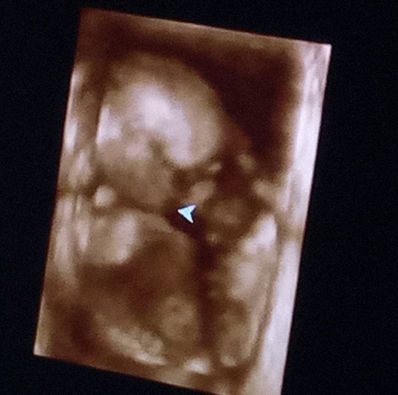

La quatrieme echographie

Voilà, on arrive à la moitié de la grossesse !

Papa et Maman ont pu avoir une vision 3D de mon joli minois. J’ai baillé et j’ai montré mes beaux yeux.

Papa dit que je ressemble à Voldemort, et Maman est fort susceptible ces temps-ci…

Elle me sent tous les jours maintenant. Le matin, je la réveille, et quand un élève me bouscule trop, je me venge !

Papa me parle tout le temps, ça me fait remuer aussi.

Le docteur a dit que les résultats de la prise de sang étaient très bons. Aucun problème génétique en vue, et maman est en forme !

Il a aussi dit que je n’ai pas beaucoup de place pour l’instant, car je grandis plus vite que ma poche d’eau.

Dans un mois j’aurai plus de place, et l’échographie sera de meilleure qualité.

Papa et Maman ont décidé de donner un indice très important ce soir, allez vite voir !